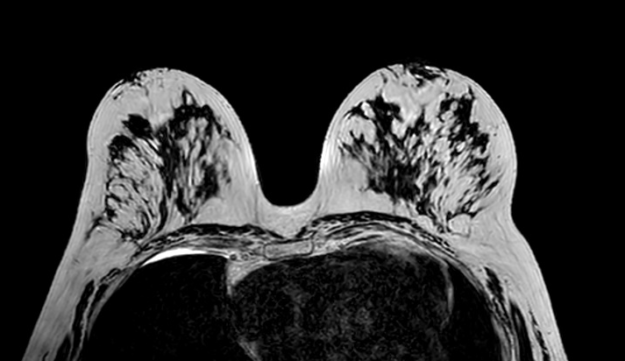

RM Avampiede

La struttura del piede, a causa dei suoi assi sempre variabili e discontinui) non consente la creazione di un protocollo standard per uno studio generale di tutto il piede. E’ quindi necessario dividere il piede in 4 zone principali: dita, metatarsi, tarso, caviglia; ciascuno con i suoi piani e protocolli specifici. STUDIO DEI METATARSI QUESTIONARIO…